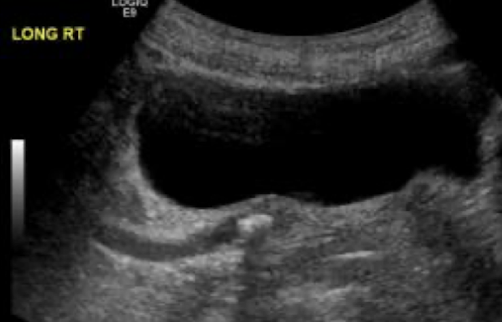

scanning techniques for imaging renals

curvilinear probe; linear probe for peds

pt. supine, decubitus, or oblique

use liver/spleen as acoustic window

have patients take in deep breaths to move diaphragm and kidneys downward

must have 3 kidney measurements (L x H x W)

TCG adjustments

compare renal cortex to liver parenchyma

renal detail may be obscured if patient has hepatocellular disease, gallstones, rib interference, or other abnormal conditions